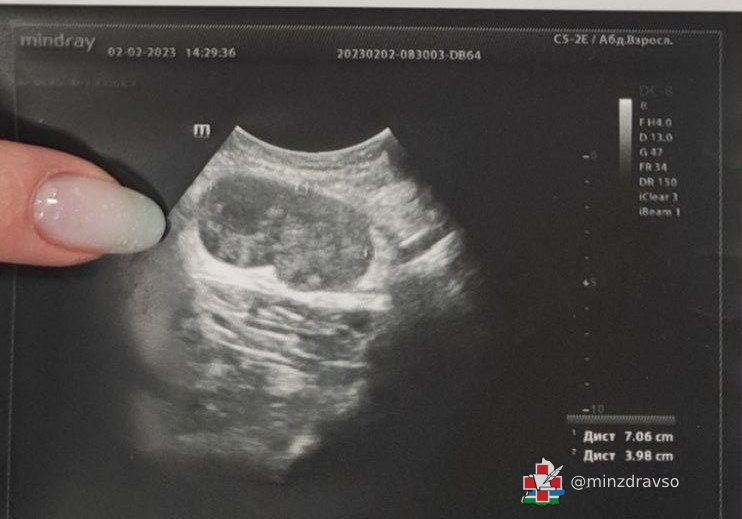

«Пациент обратился к нам с жалобами на "шарик" под мышкой. При ультразвуковом исследовании было установлено, что это увеличенный лимфоузел размером 70/40 миллиметров с изменённой структурой. Находка вызвала подозрения, пациента направили на дополнительное обследование — выполнение биопсии лимфоузла для установления точного диагноза», — рассказала врач ультразвуковой диагностики ЦГКБ №3 Жанна Краснопёрова.